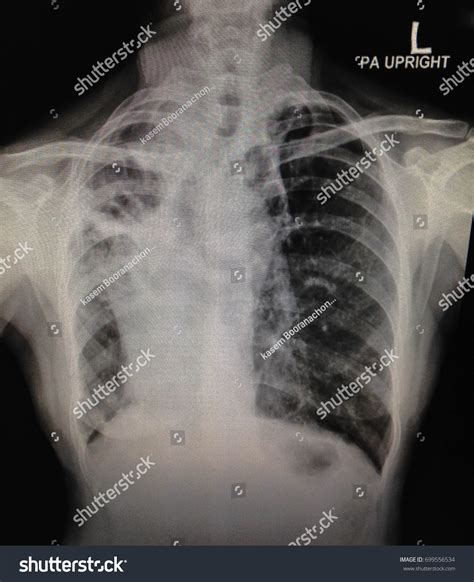

1. Lung Opacities and Consolidations

Opacities appear as white patches on the X-ray, which usually indicate that the air sacs in the lungs—normally filled with air and therefore appearing black—are filled with something else, such as fluid, pus, or blood. This is a classic sign of pneumonia or pulmonary edema.

This condition occurs when excess fluid accumulates in the pleural space, which is the thin area between the lungs and the chest wall. On an X-ray, this usually manifests as a blunting of the costophrenic angles (the sharp corners at the base of the lungs). If you see a “white-out” effect at the base of the lungs, it often points to significant fluid buildup.